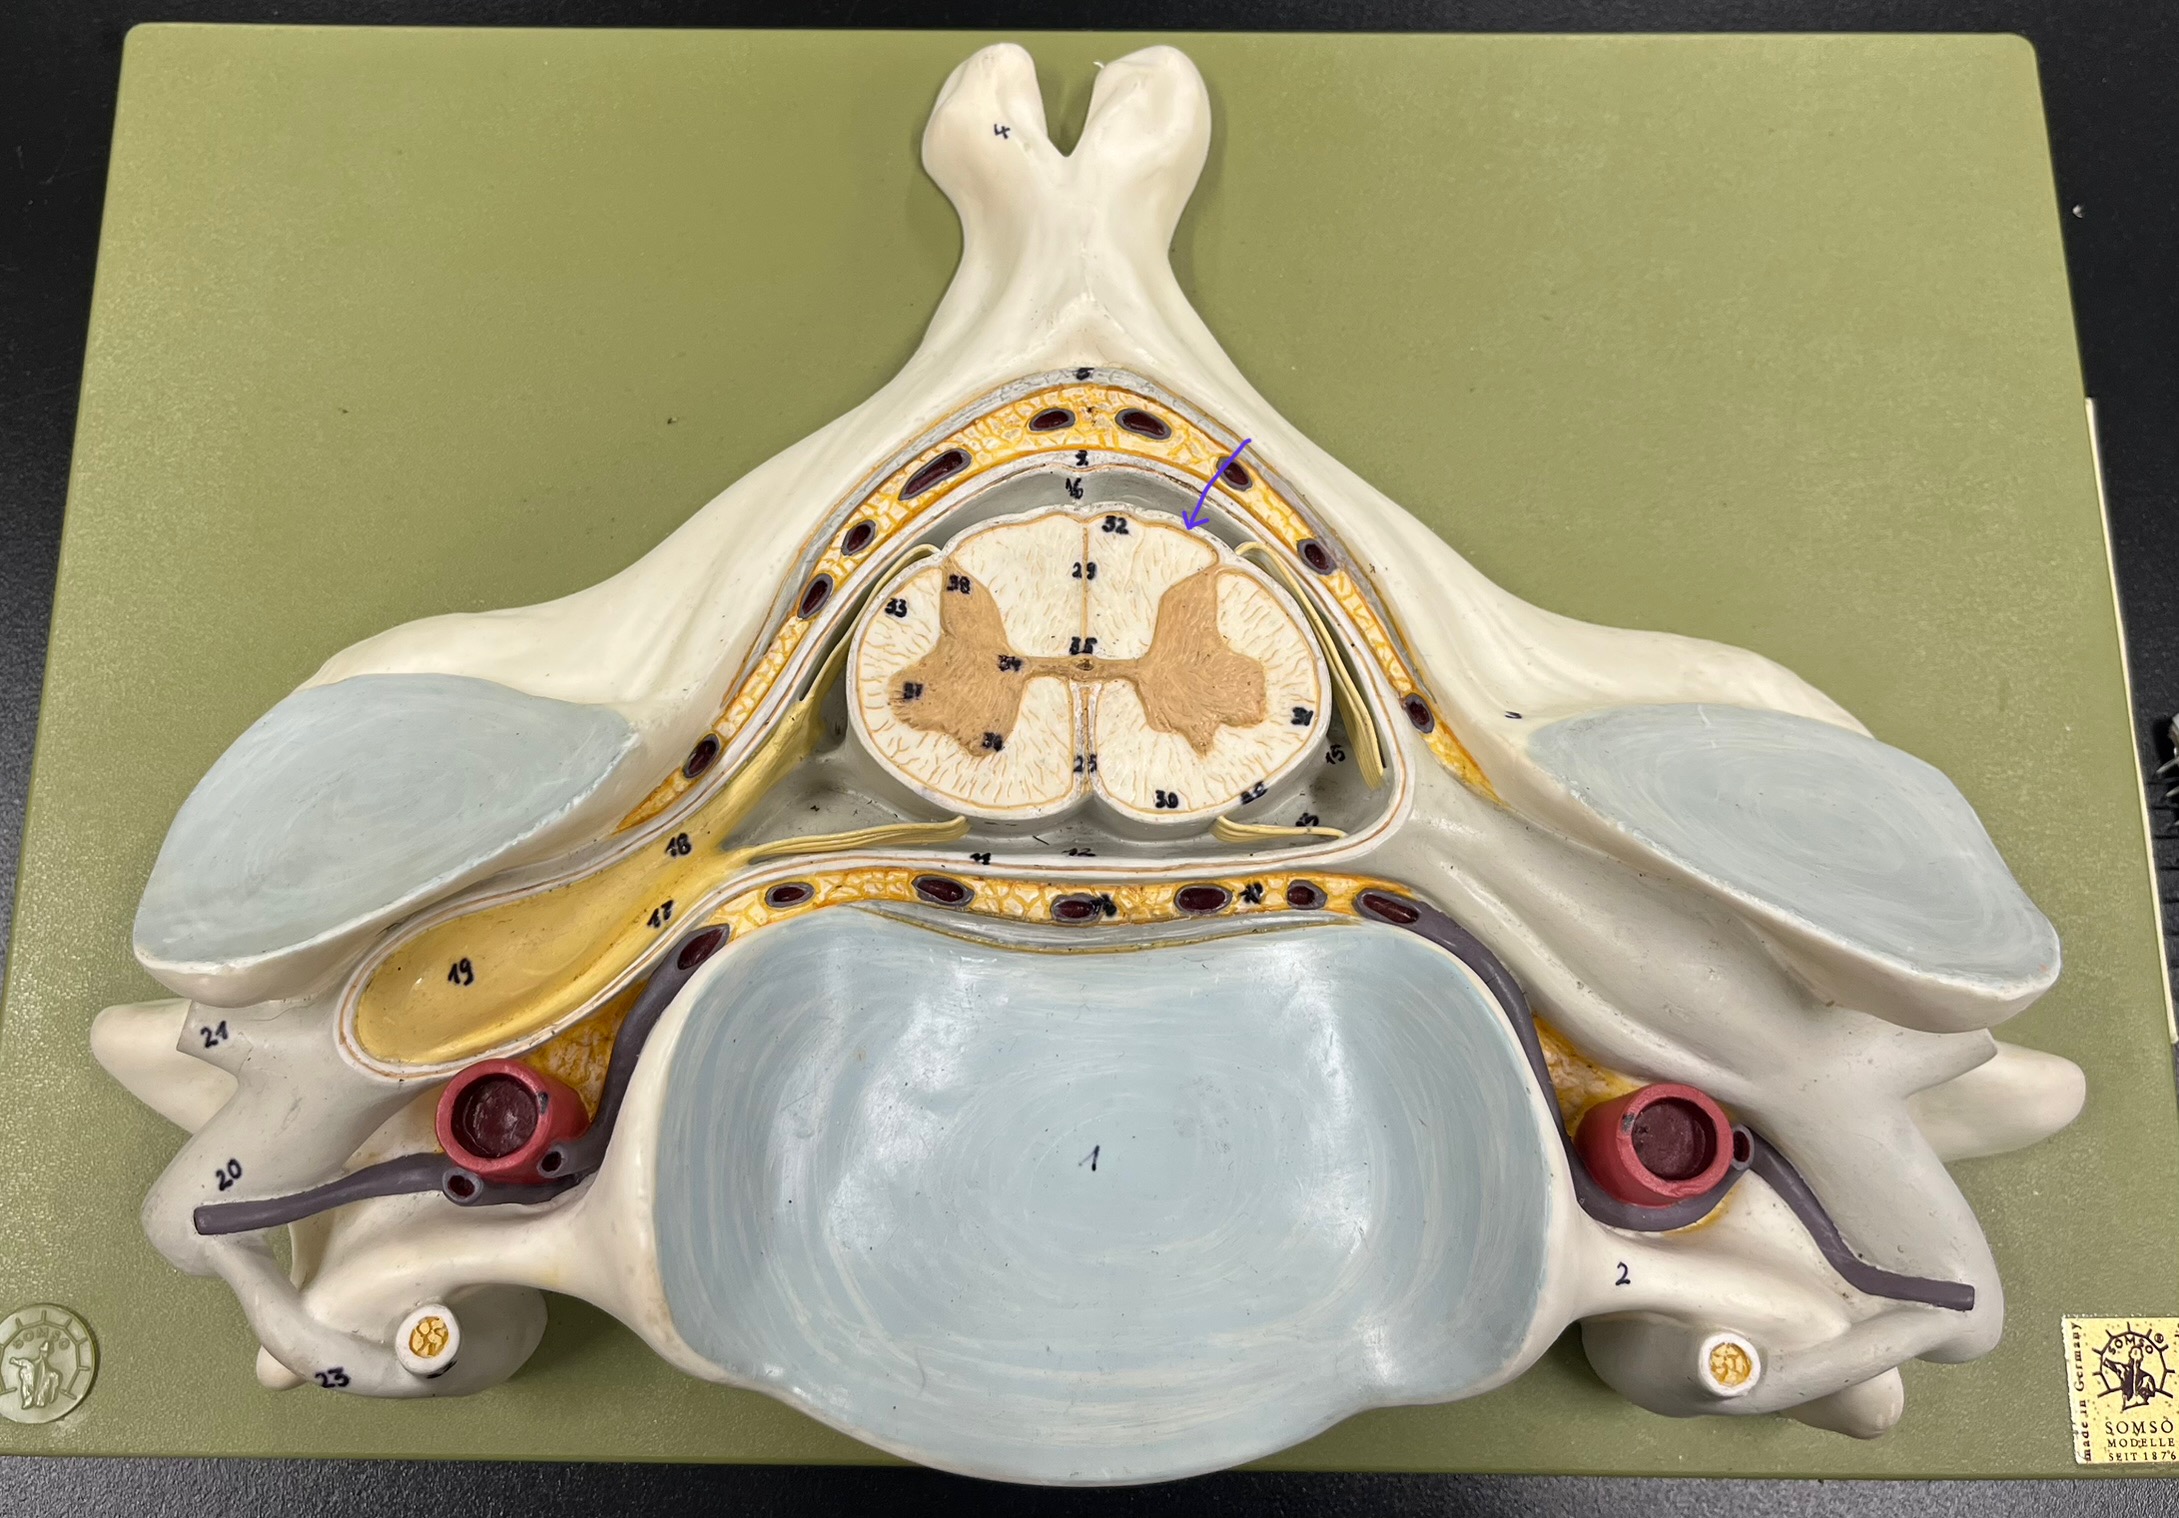

epidural space

dura mater

subdural space

arachnoid mater

subarachnoid space

pia mater

denticulate ligaments

What is the groove here?

anterior median fissure

posterior median sulcus

posterior (dorsal) horn

posterior (dorsal) horn; R—>L

anterior (ventral) horn

lateral horn (selected models)

gray commissure

central canal

anterior column

lateral column

posterior column

white commissure

posterior (dorsal) root ganglion

What is the bulb here?

posterior (dorsal) root ganglion

posterior (dorsal) root

posterior (dorsal) root

anterior (ventral) root

anterior (ventral) root

dorsal ramus

dorsal ramus

ventral ramus

ventral ramus

rami communicantes

rami communicantes

sympathetic chain ganglia

sympathetic chain ganglia